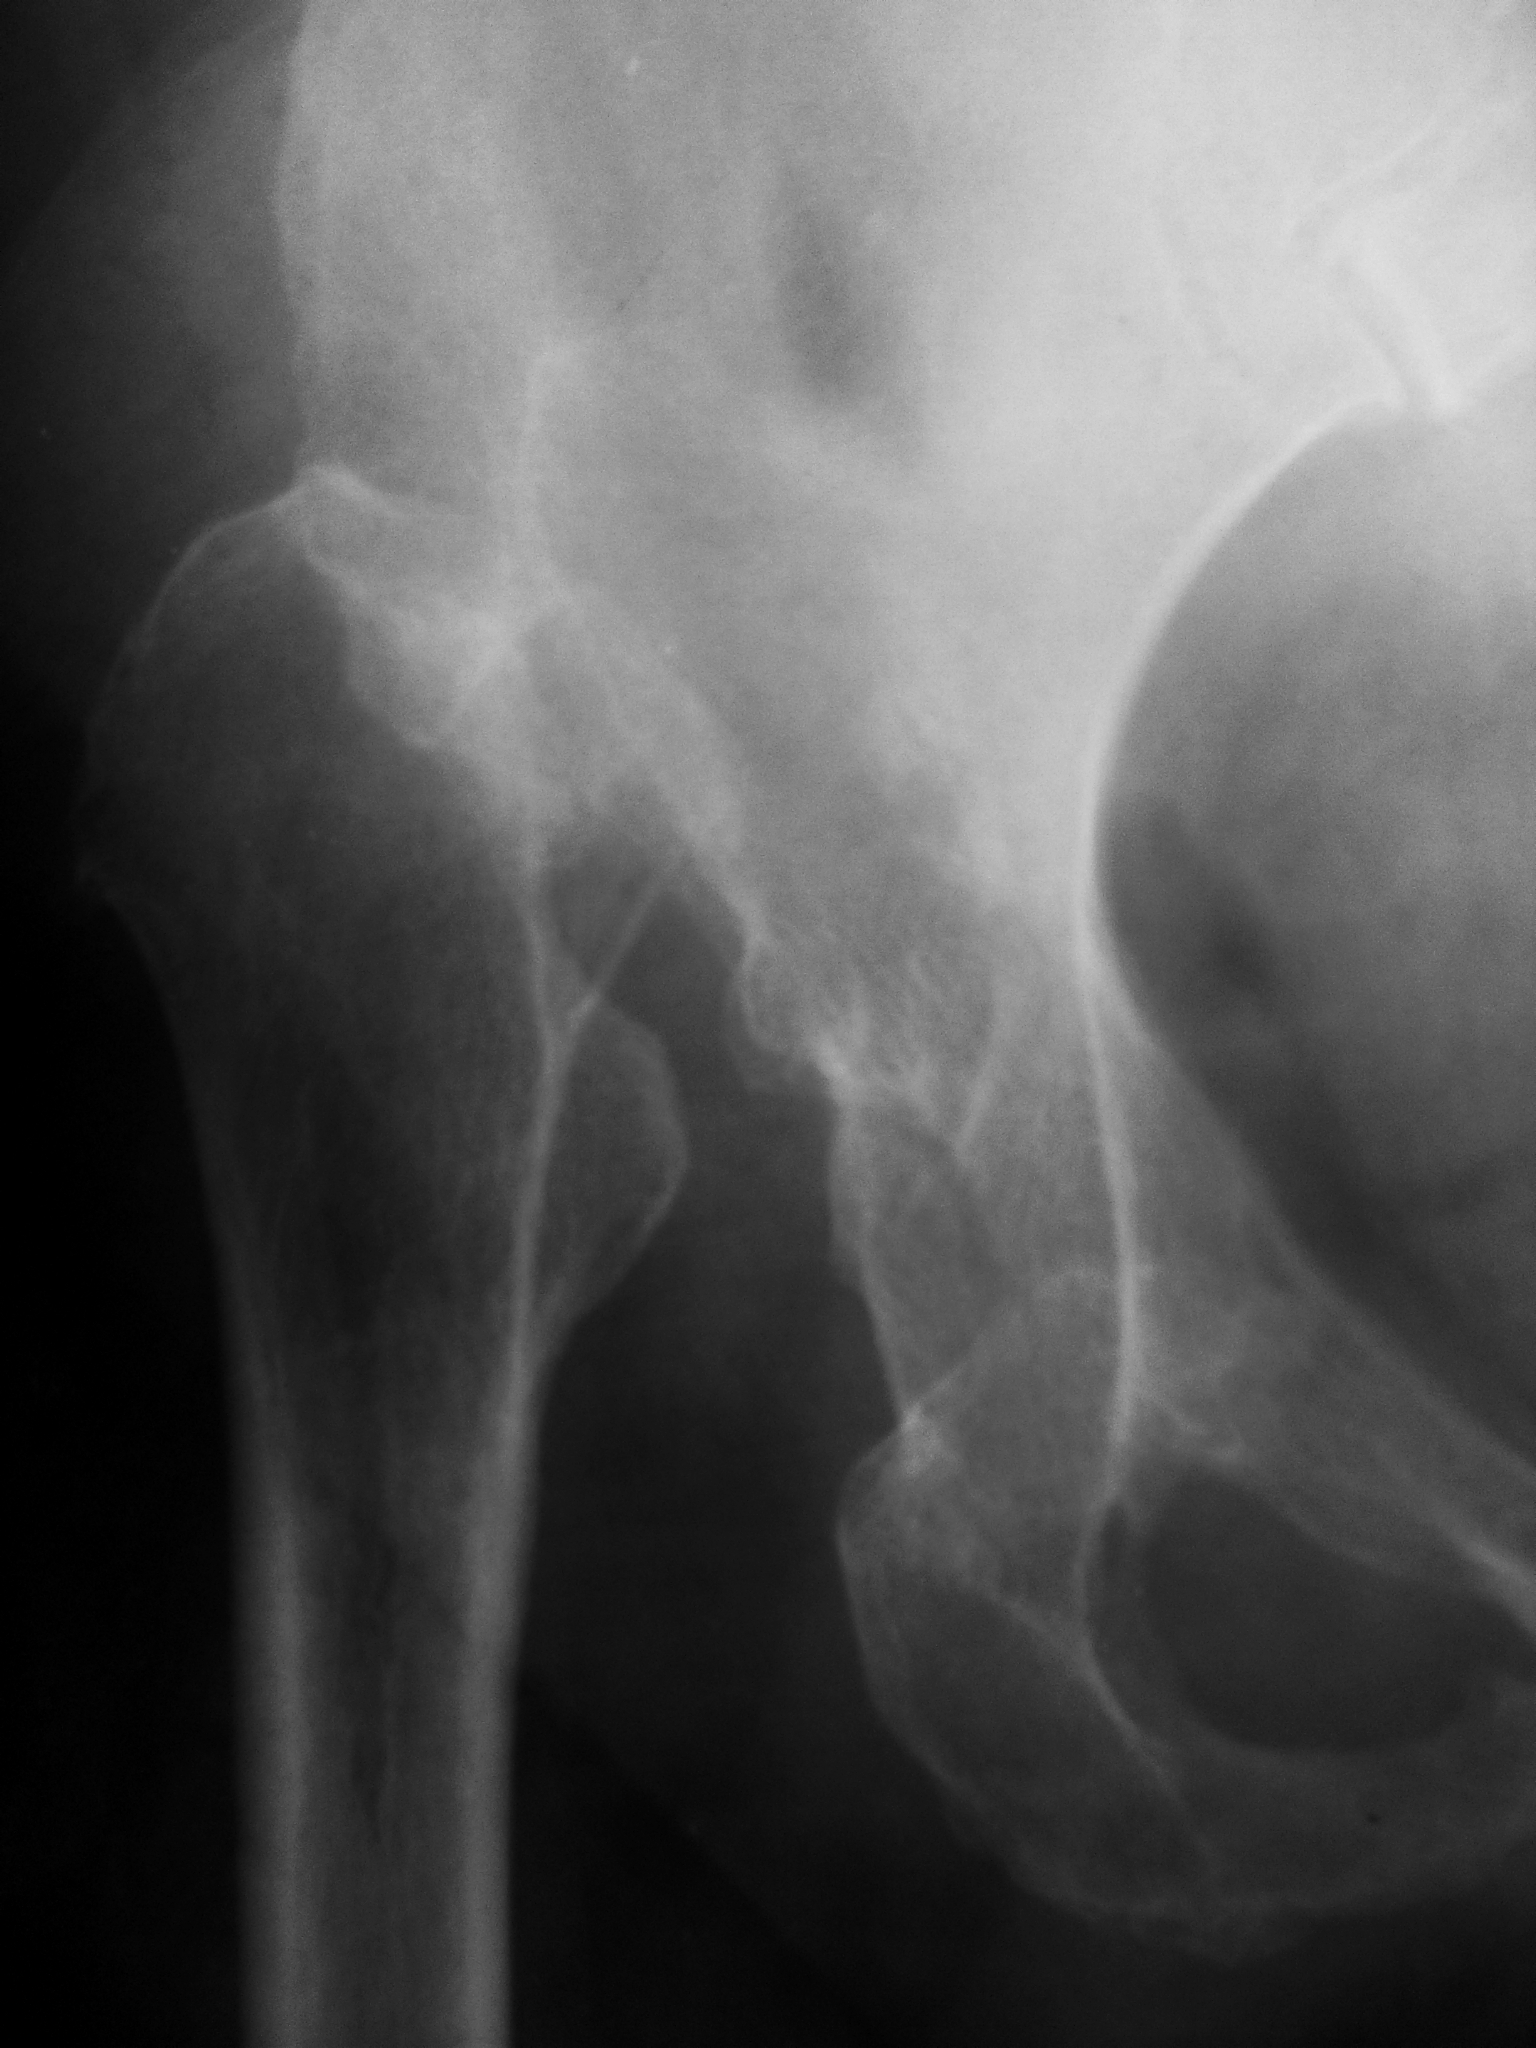

71-летняя дисплазия.

Женщине 71 год. Диагноз с раннего детства.

Врожденный вывих бедра.

Отсутствие головки и шейки с пат. вывихом правого бедра могут быть результатом туб. каксита, перенесенного в детстве.

Однако и впадина тоже отсутствует. Дисплазия врождённая и пожизненная.

Но вот седалищная кость справа усложнённой формы и структуры. Возможно, не обошлось без травмы в её долгой печальной жизни.

Вертлужной впадины сейчас действетельно нет, но контур её остался. Это значит, что когда-то была, просто, со временем зарасла за ненадобностью. Ведь природа не терпит пустоты. Так что туб. коксит не исключен. Что касается правой седалищной кости, то она выглядит по-другому, как и вся правая половина таза. Вероятно, это связано с костной атрофией и перекосом таза вправо, что в свою очередь связано с давностью процесса и укорочением правого бедра.

Правильно говорит Петрович -врождённый вивих бедра с гипоплазией головки и вертлужной впадины. Укорочение пр. нижней конечности.Подвздошный неартроз.Признаков перенесенного туберкулеза ни каких.